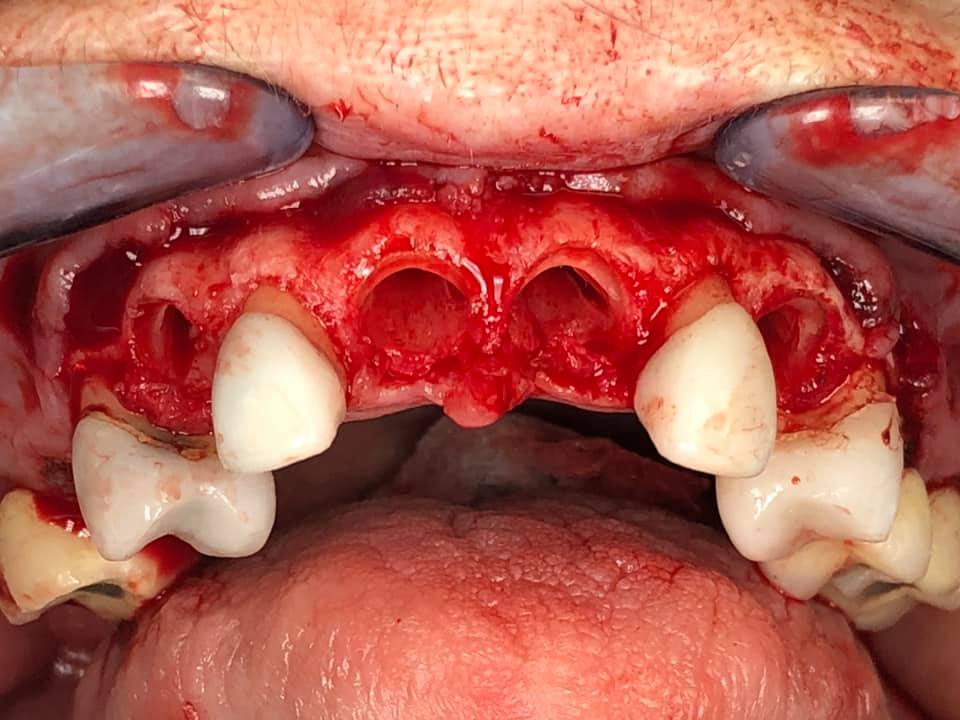

Below is a case of full arch same day temporization using the socket shield , root submergence and pontic shield techniques to preserve the site architecture . Neodent GM implants were placed in a guided fashion and same day temporization was performed using a milled PMMA.